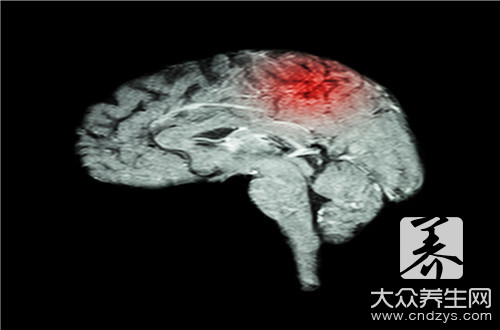

脑梗后遗症恢复方法

如今,发生脑梗的人年龄有年轻化的趋势,这种疾病的发病率与致命率都比较高,一旦发病还会有后遗症发生,给自身以及家人带来较大的痛苦。脑梗后遗症恢复方法有多种,患者在治愈后一定不能掉以轻心,每天进行有针对性的练习,以预防脑梗的再次发作。在饮食上,脑梗患者也要以清淡为主,同时要多运动。治疗脑梗发病一年后仍有肢体、语言障碍等就属于脑梗后遗症了,后遗症期的治疗重点以防止脑梗复发,改善症状为主。